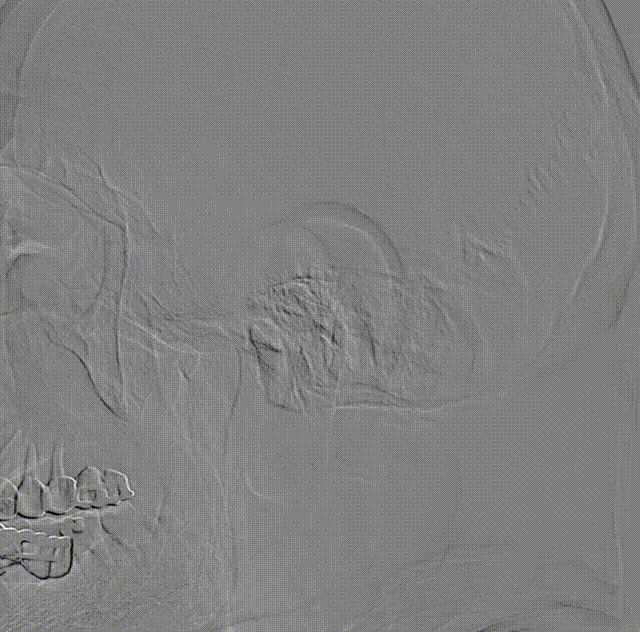

使用雅培Workhorse保护伞导丝先行通过病变狭窄处,随后将Emboshield Nav6保护伞沿导丝推送经过C1端弯曲处。借助Nav6保护伞的支撑,推送6F 115cm中间导管至C1远端,利用特洛伊木马技术将Nav6保护伞输送并放置于颈内动脉C1段。回撤中间导管,在透视状态下释放Nav6保护伞,Nav6圆周骨架在透视下显影清晰,定位准确。

将中间导管撤至颈总动脉,通过Workhorse导丝送入4mm*20mm球囊至右侧颈内动脉狭窄病变处,准确定位后以适当压力预扩狭窄病变,造影示狭窄改善不明显。撤出球囊,再次通过Workhorse导丝送入5mm*30mm球囊至狭窄病变处进行扩张,造影提示狭窄稍改善。